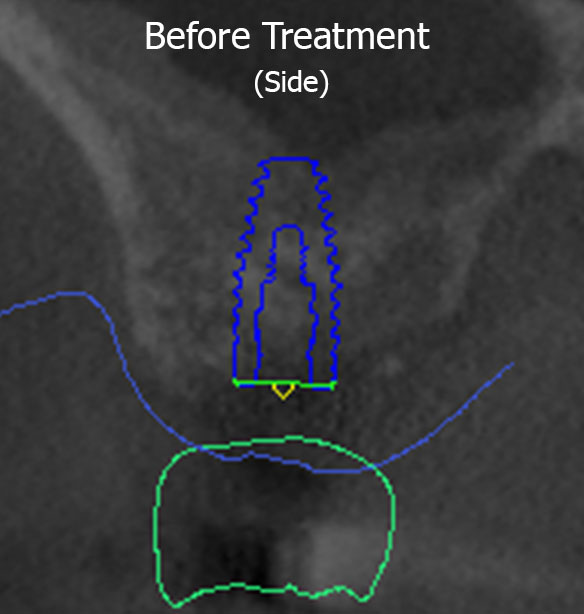

DM had a missing tooth on the top right side and wanted an implant in that area so that he could chew properly again. Planning with digital dentistry found that his sinus had grown in size as a result of the removal of the tooth (as shown by the red dotted line), meaning there was not enough height of jaw bone to support an implant in this area without causing a puncture into the sinus (shown by the transparent overlay of the planned implant site going beyond the red dotted line). As mentioned above, a puncture into the sinus can cause a serious infection with dire consequences.